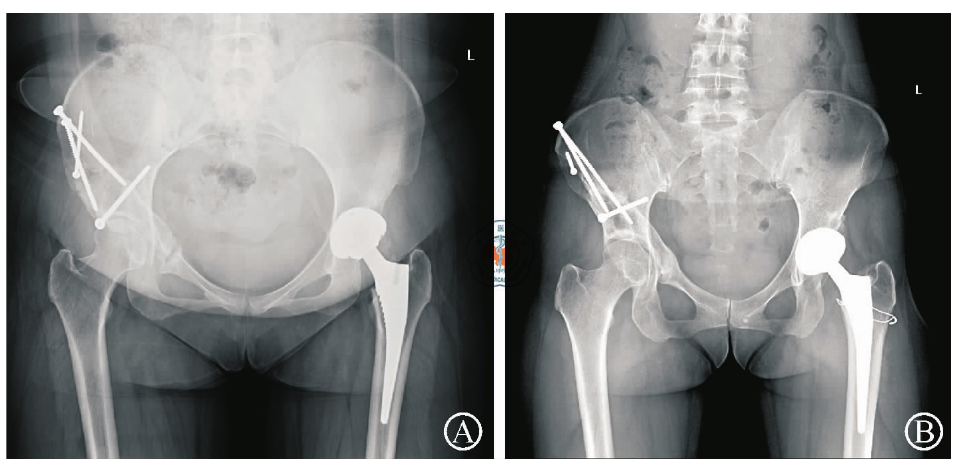

图1 典型病例患者双侧髋关节手术前后X线片。图A为患者术前站立位骨盆正位X线片,左髋关节T?nnis 2期,右髋关节T?nnis 0期;图B右侧髋臼周围截骨术后23个月随访X线片,右髋关节外侧中心角正为25°,T?nnis角矫正为0°,左髋关节T?nnis分期加重至3期;图C为患者右髋内固定取出左髋关节置换术后12个月随访X线片,右髋截骨后矫正角度未见丢失,T?nnis 0期,左髋假体位置良好未见松动迹象

图2 术后并发症患者骨盆正位X线片。图A示右髋截骨术后耻骨上支不愈合;图B示左髋THA术中股骨距骨折给予钢丝固定